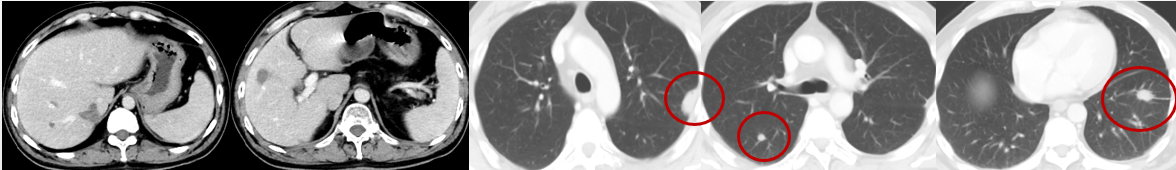

疗效评价:PD

(2019-2-18)

(2019-8-22)

右肺及左上肺多发结节,较前增多、增大。

(2019-10-2)

左肺上叶舌段一后壁空洞,两肺下叶结节,考虑转移;

肝右叶转移灶,较前变化不大。